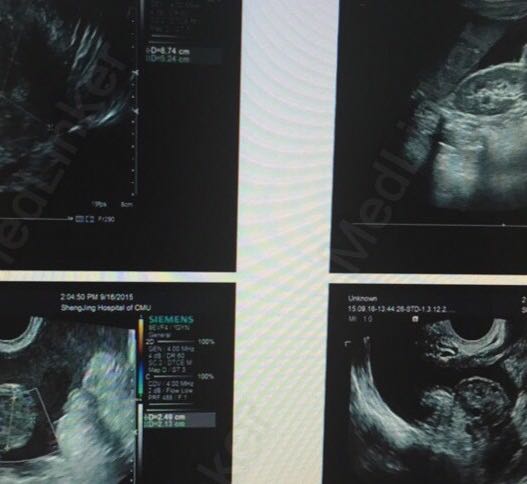

妇科检查:外阴发育正常,阴道畅,粘膜无充血,宫颈常大、光滑,腹腔内大量积液,子宫及双附件触诊不清。 全腹增强CT:双附件区包块,提示卵巢Ca;伴大网膜转移;腹膜转移;大量腹腔、盆腔积液;双侧心膈角可见淋巴结显示; PET-CT:双附件区FDG高代谢结节,建议首先完善结核相关检查除外结核,结合肿瘤标志物,必要时进一步手术活检。胸骨柄右侧、双侧肺门及右侧心膈角区稍高代谢结节,考虑淋巴结受累,结合附件病灶性质考虑。腹盆腔大量积液,腹膜多发结节状增厚,腹腔脂肪间隙FDG代谢增高,结合附件病灶性质首先除外结核性腹膜炎,结合腹水肿瘤标志物及瘤细胞学等相关指标。双肺内多叶段磨玻璃密度斑片影,考虑感染性病变可能大,建议首先除外结核。 患者肿瘤标记物正常。